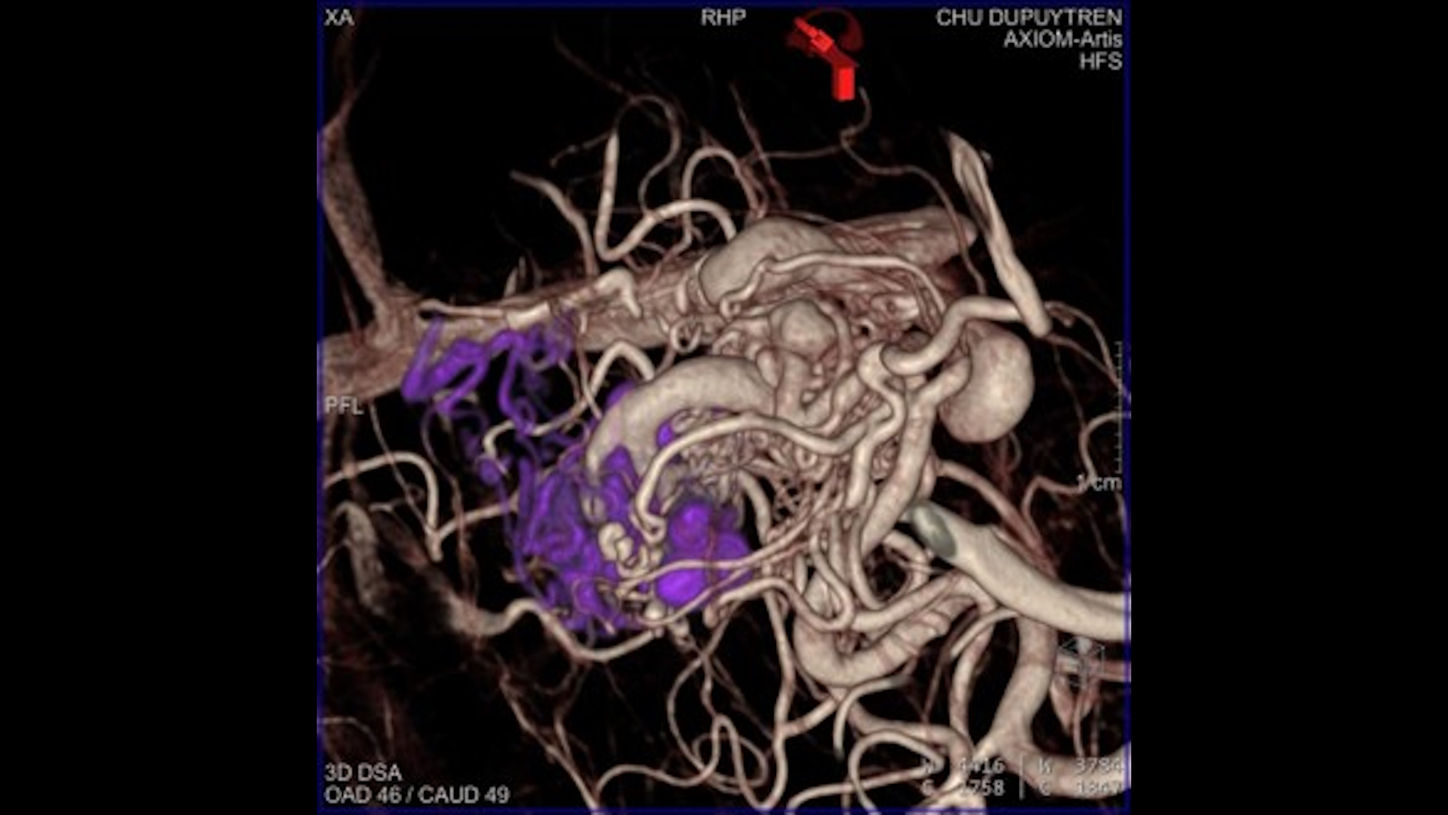

NeurologyDiscover our solutions for imaging and image guided therapy in Neurology

Neurological disorders can threaten the fundamental hope of a happy and independent life, spent with the people we care about. Helping patients achieve their highest potential independence by supporting your diagnosis and treatment is what we strive for.